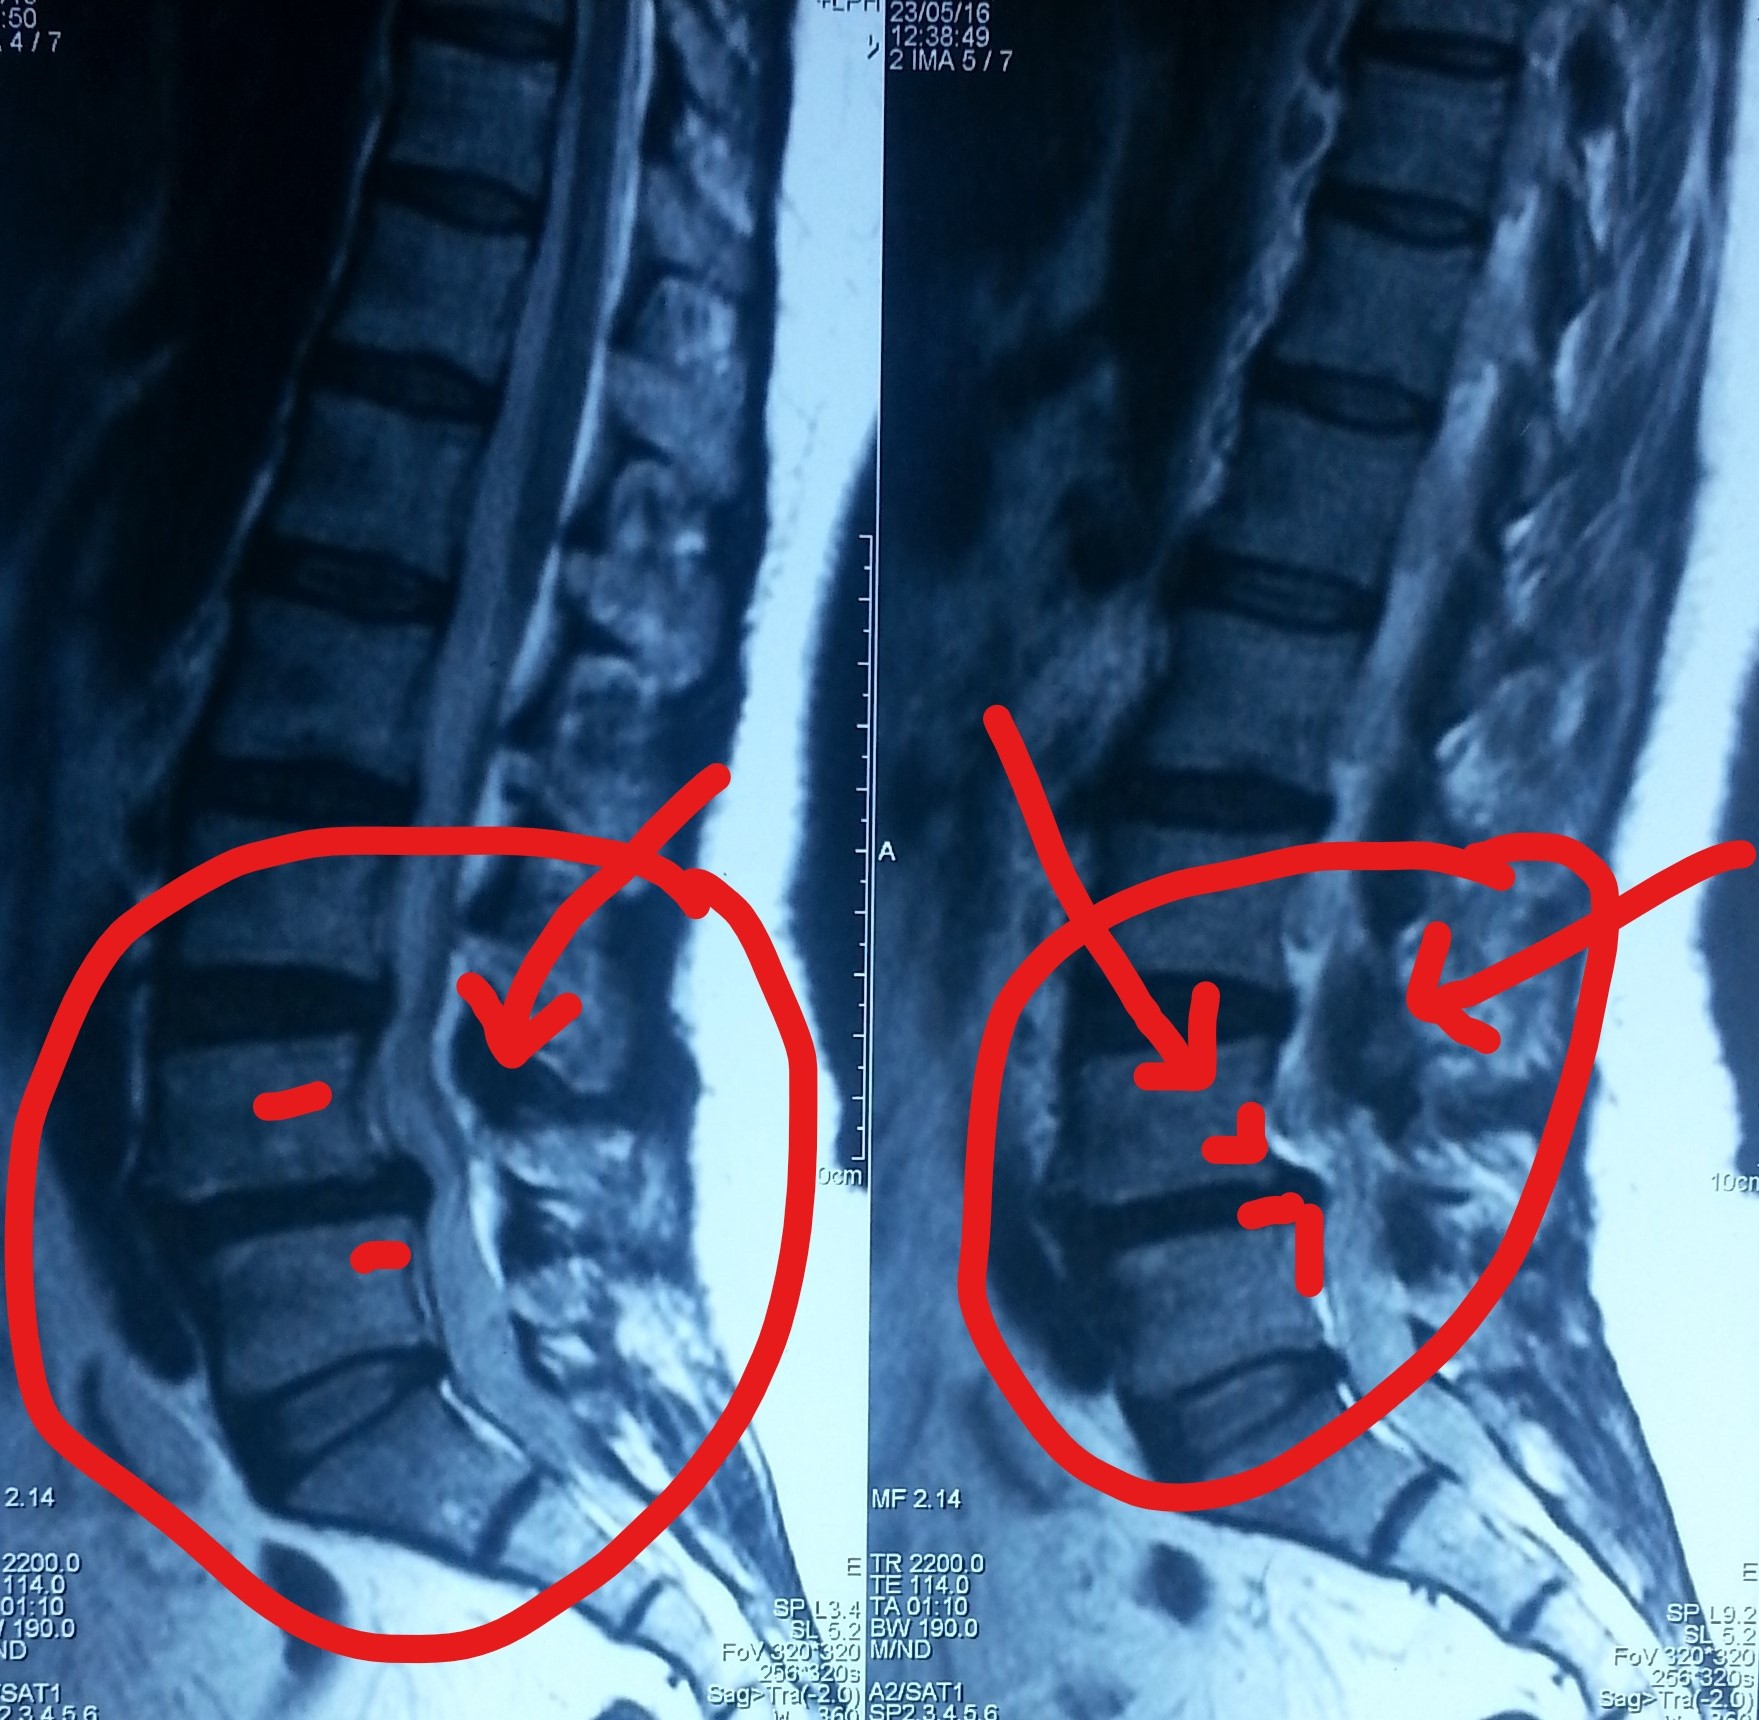

تزحزح بالفقرات القطنية مع ضيق بالقناة العصبية قبل وبعد الجراحة

lumbar displacement with neural canal stenosis before and after surgery

A successful surgery was performed to treat lumbar spondylolisthesis accompanied by spinal stenosis. This condition causes severe back and leg pain due to pressure on spinal nerves, significantly affecting quality of life and mobility.